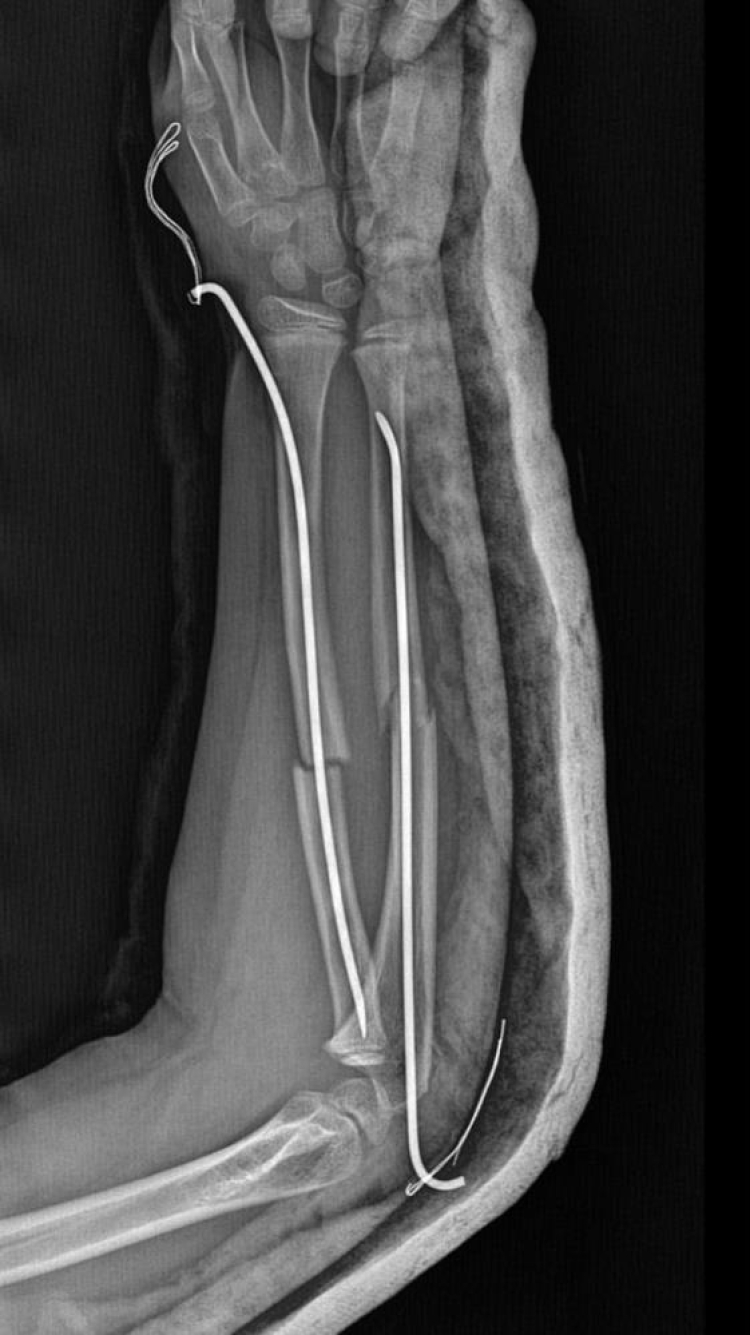

İstanbul'un Büyükçekmece ilçesinde, 9 yaşındaki bir çocuk 8 yaşındaki arkadaşının kolunu 2 yerinden kırdı. Çocuk ameliyata alınarak koluna platinler takıldı. Savcılık "Çocukların yaşları 12'den küçük olduğu için kovuşturmaya yer yoktur" kararı verdi. Haftalardır çocukları okula gidemeyen aile karara itiraz etti. Suça sürüklenen çocuğa sorulduğunda ise, "beni öğretmene şikayet ettiği için intikamını aldım" dediği ileri sürüldü.

Olay, geçtiğimiz ay Büyükçekmece Tepecik'te bulunan bir ilkokulda meydana geldi. İddiaya göre 8 yaşındaki Y.K.Ş. okulda bir süredir kendisini rahatsız eden 9 yaşındaki çocuk tarafından darp edilerek kolu ikiye katlandı. Y.K.Ş.'nin 2'ye katlanan kolu 2 ayrı yerinden kırıldı. Öğretmenler Y.K.Ş.'nin ailesini arayarak, ‘oğlunuz arkadaşıyla kavga etti duvara çarptı' denildi. Oğlunu okuldan alıp hastaneye götüren anne Songül Gökdemir, oğlunun kolunun 2 ayrı yerinden kırıldığını öğrenip ameliyata alınacağını duyduğunda büyük şok yaşadı. Konuyla ilgili anne Gökdemir savcılığa giderek şikayetçi oldu. Savcılıktan ise 'söz konusu Suça Sürüklenen Çocuğun yaşının 12'den küçük olduğu gerekçesi ile kovuşturmaya yer yoktur' kararı çıktı. Anne Gökdemir karara itiraz ederken mağdur Y.K.Ş. ise haftalardır okula gidemiyor. Eğitimi aksayan çocuğun 2 hafta sonra ise platinlerinin çıkarılması için yeniden ameliyata gireceği öğrenildi.